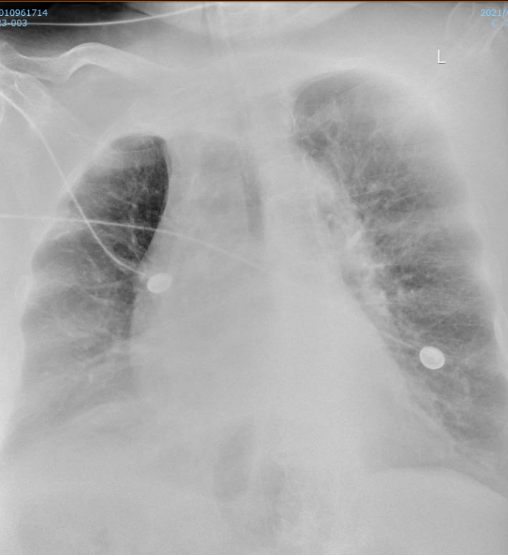

• 胸部X线:双肺弥漫性渗出改变(图1)

图1  患者胸部X线片